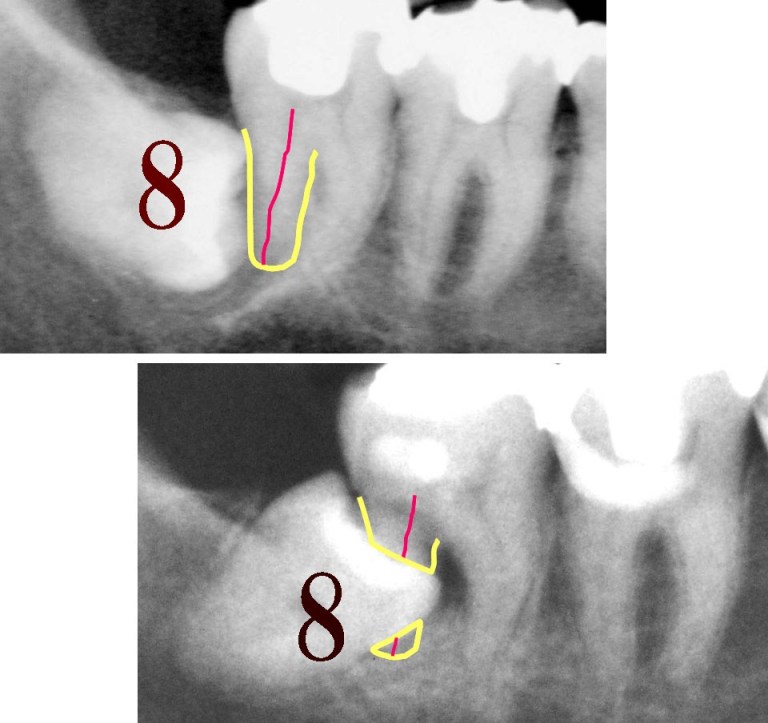

見事にまっぷたつに割れた歯です。

この写真を見て下さいね。

8番目の歯というのは「親しらず」のことです。

吉本歯科医院では、親知らずは

ほぼ9割の患者さんに対しては「抜いたほうがいいですよ」とお伝えしています。

その理由は

この患者さんは

親知らず(8番目の歯)を抜かずにおいておいたことで

お隣の7番目が押され

3度3度の食事の力や

寝ている間の歯軋りの力により

押され、なんとお隣の歯の神経がブチリと切断されてしまったのです。

親知らず(8番目)の歯が原因でお隣の7番目、6番目の歯が

どんどん押されてドミノ倒しのように倒れていきます。

8(親知らず)が押す力は

実は止まりません。

止まっていてくれないんです。

ガンガンガンガンと親知らずは

押し続け7番目6番目の歯を押し続けます。

ついには

親知らずのお隣の7番目の歯の神経を

ブチリっと切断してしまいました。

歯が痛くなる原因は

ばい菌だけが原因ではありません。

ばい菌だけが原因だ

と思い込んでいると

将来、歯を失う危険性があります。